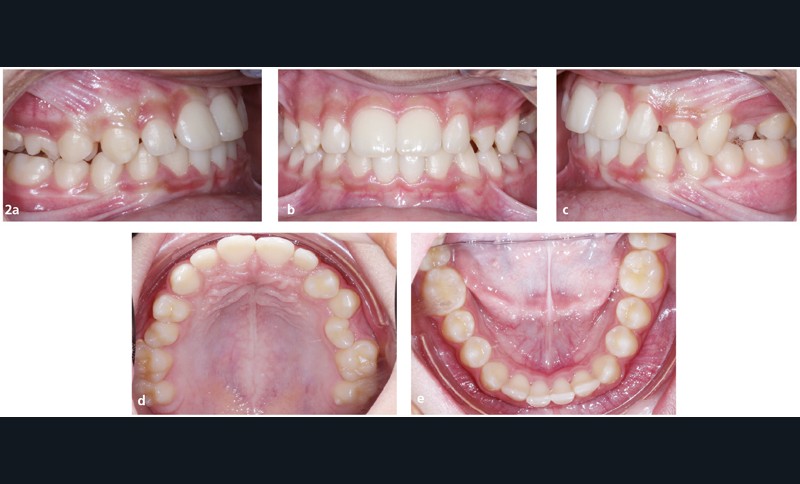

Paulo D., 13 ans, consulte pour un motif esthétique. Il présente une ligne du sourire non harmonieuse, avec la rotation de 24 en place de 23, un sourire gingival à droite et les milieux incisifs non alignés entre eux (fig. 1).

Sur le plan occlusal et dentaire, on observe une classe III molaire et canine à gauche, une proalvéolie maxillaire, une occlusion inversée au niveau des 15/46 et 25/35-36, une non concordance des milieux incisifs et une transposition complète de 23 et 24 (fig. 2 et 3).